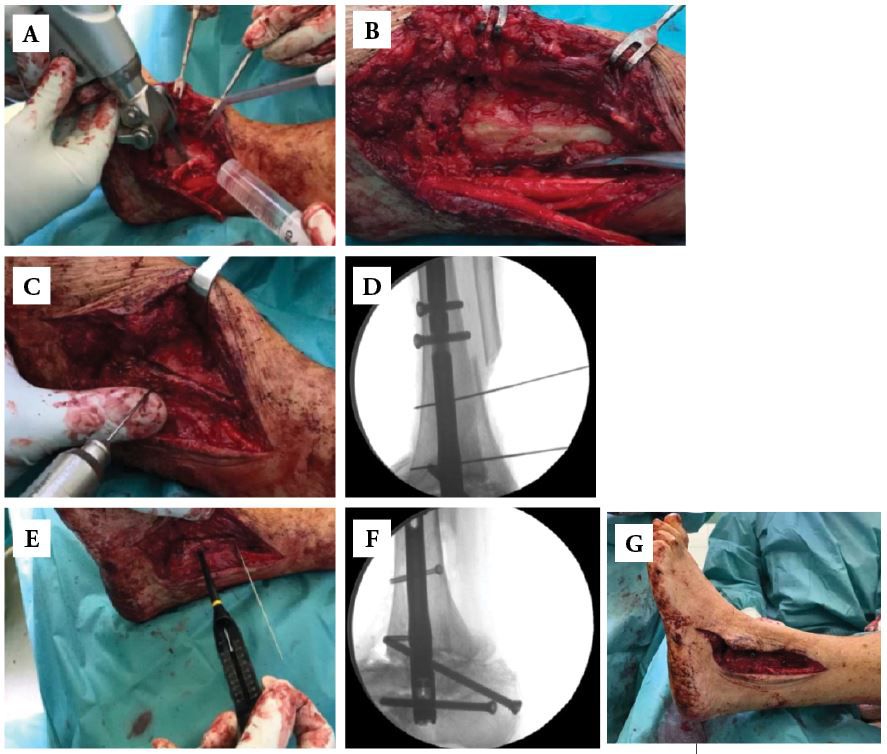

• Severe hindfoot arthritis with significant deformity or instability (Figs. 1-A through 1-G).

Step 4. Ankle and subtalar joints preparation

• Take out ankle articular surfaces with a chisel or burr. Hintermann spreader facilitates holding articular surfaces apart. Try to anatomically remove the cartilage. In case of hindfoot malalignment correction asymmetric bone cuts are necessary additionally (Figs. 5-A and 5-B).

• Similarly, take away articular surfaces of the subtalar joint. Lamina spreader provides adequate exposure (Fig. 5-C).

• Freshen up subchondral sclerotic areas with a drill 2.0 mm (Fig. 5-D).